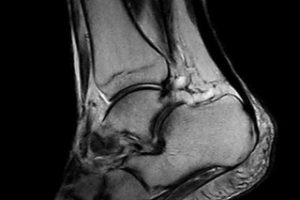

When you need high-quality extremity MRI, the O-scan dedicated MRI system is the perfect fit. The O-scan system’s complete range of extremity imaging capabilities, intuitive operation, and compact footprint combine to provide the optimal solution for both patients and practices.